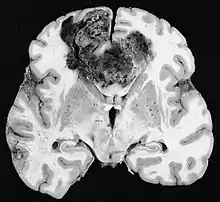

Glioblastome

Les tumeurs des cellules gliales les plus courantes et les plus malignes sont les glioblastomes. Ils consistent en une masse hétérogène de cellules d'astrocytome peu différenciées principalement chez l'adulte. Ils surviennent généralement dans les hémisphères cérébraux, plus rarement dans le tronc cérébral ou la moelle épinière. Sauf dans de très rares cas, comme toutes les tumeurs cérébrales, elles ne s'étendent pas au-delà des structures du système nerveux central.

Le glioblastome peut provenir d'une forme diffuse (II. grade) ou un astrocytome anaplasique (III. grade) développer. Dans ce dernier cas, il est dit secondaire. Cependant, lorsqu'elle survient sans antécédent ni signe de malignité antérieure, on parle de maladie primaire. Les glioblastomes sont traités par chirurgie, radiothérapie et chimiothérapie. Ils sont difficiles à guérir et rares sont les cas qui survivent au-delà de trois ans.

Les métastases cérébrales sont les néoplasmes intracrâniens les plus courants chez les adultes, étant dix fois plus fréquents que les tumeurs cérébrales primaires. Ils marchent à 20 jusqu'à 40 pour cent des adultes atteints de cancer et sont principalement associés au cancer du poumon et du sein et au mélanome . Ces lésions résultent de la propagation des cellules cancéreuses dans la circulation sanguine et surviennent le plus souvent à la jonction de la matière grise et blanche, où la section transversale des vaisseaux sanguins change, emprisonnant les embolies de cellules tumorales . 80 % des lésions surviennent dans les hémisphères cérébraux, 15 pour cent dans le cervelet et 5 pour cent dans le tronc cérébral. Environ 80 % des patients ont des antécédents de cancer systémique et 70 pour cent ont de multiples métastases cérébrales.